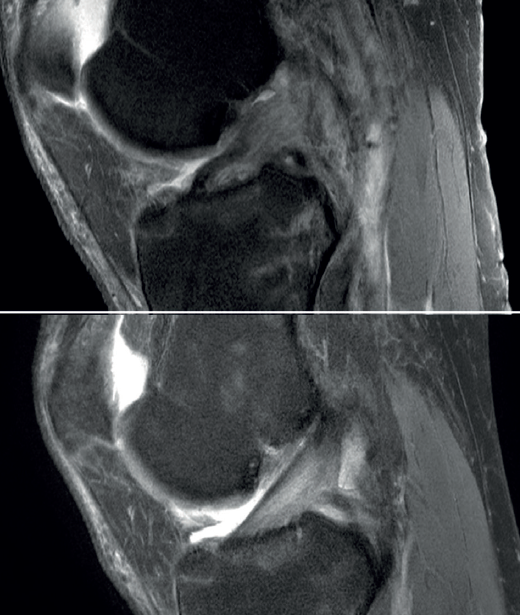

The main indication for primary ACL repair is in patients with high-grade complete or partial tears corresponding to types 1 or 2 of the original Shermanclassification(7), i.e. in avulsions of the femoral insertion (type 1) or in proximal tears leaving 75-90% of the distal ligament intact (type 2). In any case, good quality of the remaining tissue is essential. It should be noted that the incidence of tears of this kind appears to be greater in individuals over 35 years of age(7). This is not a problem, given that the incidence of re-rupture following ACL repair is higher in younger patients under 21 years of age(8,9).

With regard to the timing of surgery, the operation is ideally performed within 6 weeks of the injury(10,11,12), although good results have also been published repairing chronic tears in which the torn ACL stump heals over the posterior cruciate ligament (PCL)(13,14).

The possibility of repairing an ACL tear depends on the characteristics of the tear itself and of the patient. With regard to the tear, according to the Sherman classification , 22% of all ACL tears are considered to correspond to type 1 (avulsions of the femoral insertion), 90% of which present sufficient tissue quality to indicate repair(23).